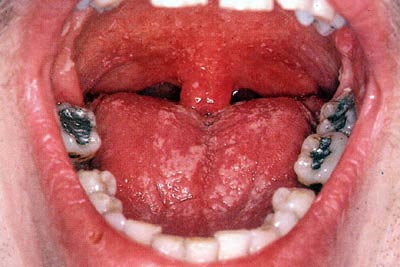

Молочница может быть слабой инфекцией, не вызывающей никаких симптомов. Симптомы обычно проявляются при развитии заболевания. Как правило, заболевание развивается внезапно, но она может стать хронической и существовать в течение длительного времени. Общим признаком молочницы является наличие кремово-белых поражений во рту:

Как правило, такие пятна образуются на языке или внутренней щеке, но иногда в верхней части ротовой полости, на дёснах, миндалинах или задней стенке горла. Поражения, которые внешне напоминают творог, могут быть безболезненными или немного кровоточить, когда вы трёте их или чистите зубы. В тяжелых случаях поражение может распространяться в пищевод.

- Белые пятна на языке и во рту. Ткани вокруг ранок могут быть красными и болезненными. При натирании (например, во время чистки зубов) поражения могут немного кровоточить.

Ваш стоматолог может выявить молочницу при осмотре ротовой полости, заметив характерные белые язвы на губах, языке или щеках. Легкое очищение поражений может вызвать покраснение мягких тканей, которые могут немного кровоточить. Микроскопическое исследование пораженных участков поможет подтвердить диагноз.